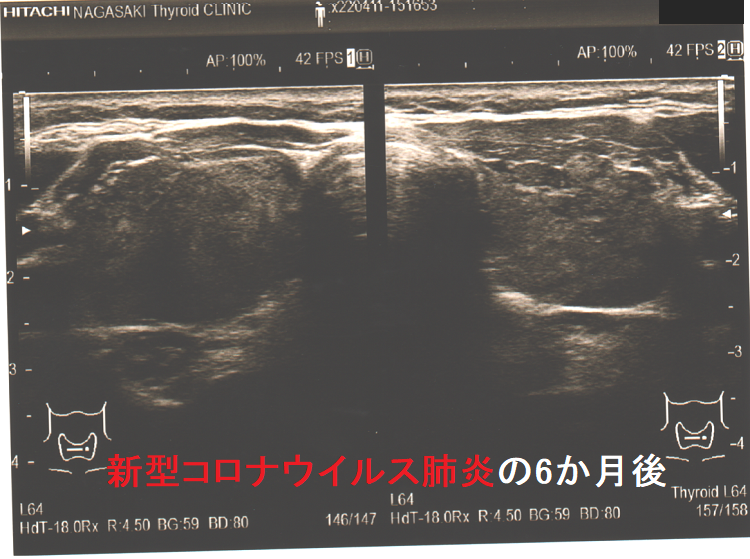

下の写真は、新型コロナウイルス肺炎に罹った甲状腺機能正常橋本病患者の感染前後計12か月の超音波(エコー)画像です。新型コロナウイルス肺炎になる6か月前と6カ月後に、1年に1回の定期検査で長崎甲状腺クリニック(大阪)を訪れていました。新型コロナウイルス肺炎発症時の甲状腺機能は不明ですが、少なくとも6カ月後は正常でした。しかし、発症前に比べて甲状腺は腫大し、腹側(写真下部)の低エコー領域(黒い部分)が拡大しており、橋本病の炎症が増悪したと推察されます。新型コロナウイルス肺炎発症時には破壊性甲状腺炎(無痛性甲状腺炎)を起こしていても不思議ではありません。